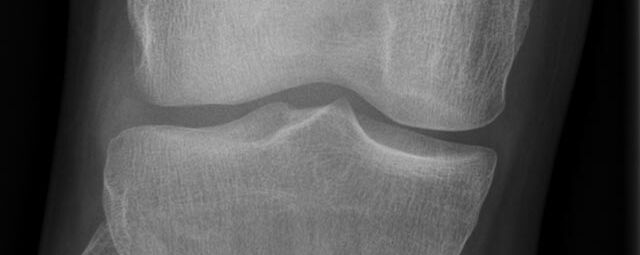

Konventionelles Röntgen

Der Begriff Röntgen, oder auch Röntgendiagnostik bezeichnet ein Verfahren in der Radiologie, bei dem von einer Röntgenröhre elektromagnetische Wellen (Röntgenstrahlen) durch die zu untersuchende Körperregion des Patienten gesendet werden. Je nach Dichte der Gewebeart des Körpers (z.B. Knochen oder Lunge) werden die Röntgenstrahlen im Körper unterschiedlich stark abgeschwächt. Ein digitaler Detektor empfängt dann die Röntgenstrahlen, die in abgeschwächter Form den Körper wieder verlassen haben. Daraus wird das Röntgenbild erzeugt.

Die Röntgenuntersuchung ist weiterhin eine unverzichtbare Basisdiagnostik. Viele Fragen können in der medizinischen Diagnostik mit einer konventionellen Röntgenaufnahme geklärt werden.